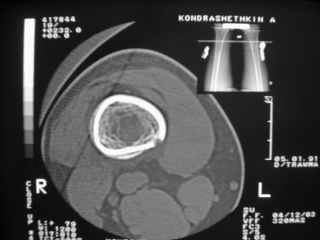

Здравствуйте, уважаемые коллеги!Представляю вашему вниманию интересный случай и пока что непонятный для меня в диагностическом плане. На днях в наше отделение (детской ортопедии и травматологии) поступил 13-летний мальчик по направлению из поликлиники с диагнозом: остеома нижней трети правого бедра.

Анамнез практически никакой: в следствие травмы (растяжение связок коленного сустава) от 07.11.2004 выполнены Rg-граммы в травмпункте и обнаружено опухолевидное образование. Первичные Rg-граммы я не публикую, так как они заметно худшего качества, да и динамики за прошедшие три недели не отражают. Болевой синдром купирован в течение трёх дней. В настоящий момент мальчика ничего не беспокоит. Ходьба не нарушена, опухоль пальпируется с трудом по задней поверхности в н\3 правого бедра, пальпация безболезненна, объем движений в суставах правой нижней конечности полный и симметричный. Кожа над опухолью не изменена.В нашей клинике проведено дополнительное обследование: общие анализы крови и мочи, биохимия крови без особенностей. Выполнены Rg-граммы на цифровом Siemens обычные и продольные томограммы срезами 3-5 мм, а также компьютерная томография поперечными срезами по 5 мм. Прошу обратить внимание, что на приведённых томограммах видны две полости 10х15 мм и 15х60 мм. Также имеются два опухолевидных образований наслаивающихся друг на друга: уплощённое и вытянутое 10х100 мм и элипсовидной формы 15х30 мм. Это хорошо заметно на фото a_1.jpg c_1.jpg и d_1.jpg. Плотность внутри полостей 125% от плотности костномозгового канала, плотность наружного опухолевидного образования 55% от плотности кортикального слоя. Также отмечается линия перелома по центру наружного опухолевидного образования.Исходя из полученных данных мнения в плане диагноза несколько разделились от 1)сочетания кортикальной фиброзной дисплазии и латентно протекавшего маршевого перелома н\3 правого бедра до 2)остеосаркомы. В отношении первого варианта не сходится отсутствие клиники при переломе такой крупной кости как бедро, второй вариант вообще оставлю без комментария, ибо некомпетентен. Хотелось бы услышать мнения коллег, с удовольствием ознакомлюсь с любыми предположениями и замечаниями.С уважением, Александр Е. КлоковОтделение детской ортопедии и травматологииБСМП г. Мурманска.